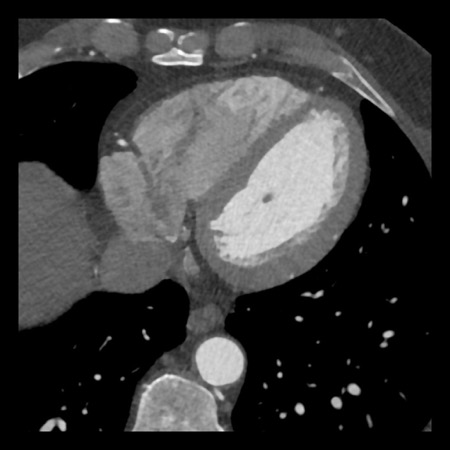

case 4 – CAD-RADS 3/P1/I+ thrombus left ventricle

First, scroll through the CTA images.

How would you describe the findings on the coronary CTA?

The findings are:

- Moderate (50-69%)

stenosis in the proximal LAD caused by a non-calcified plaque. - Variant of

sinoatrial (SA) nodal artery. The artery usually arises from the RCA as a second

branch after the conus artery, however in this case it arises from the LCX,

courses behind the aorta, anastomosing with the right atrium and with a small

branch supplies the SA-node of the heart. - Thrombus in the

apex of the left ventricle. - CTP was performed

in this patient. CTP showed a perfusion defect at stress imaging in the

territory of the LAD (I+), at rest no perfusion defect was visible.

This patient classifies as CAD-RADS 3/P1/I+, which means

this patient requires further investigation.